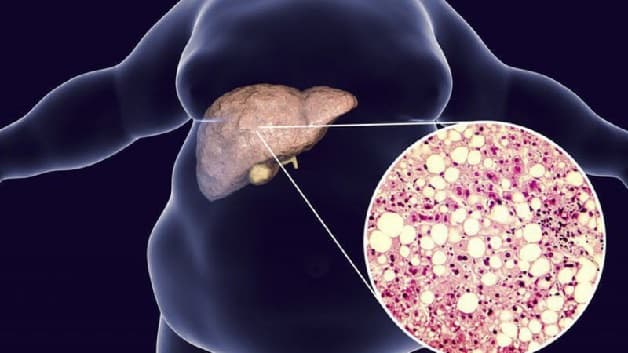

Gan nhiễm mỡ mức độ 4 là tình trạng 75% tổng trọng lượng gan bị xâm chiếm bởi mỡ. Trong trường hợp này, gan không còn khả năng tự phục hồi, bù trừ và dễ bị tổn thương. Gan nhiễm mỡ ở cấp độ này thường đi kèm với viêm gan hoặc xơ gan. Nếu không được điều trị kịp thời, bệnh nhân có nguy cơ cao bị suy yếu chức năng gan và có thể dẫn đến xơ gan mất bù.

Sự nguy hiểm của gan nhiễm mỡ mức độ 4 nằm ở khả năng gây ra các biến chứng sức khỏe nghiêm trọng, bao gồm viêm gan mạn tính, ung thư gan, tiểu đường, tăng huyết áp và tăng nguy cơ mắc các bệnh lý tim mạch. Vì vậy, việc xác định và điều trị gan nhiễm mỡ độ 4 là rất quan trọng để bảo vệ sức khỏe gan và toàn bộ cơ thể.

Gan nhiễm mỡ mức độ 4 là bệnh lý nguy hiểm, thường đi kèm với viêm gan và xơ gan